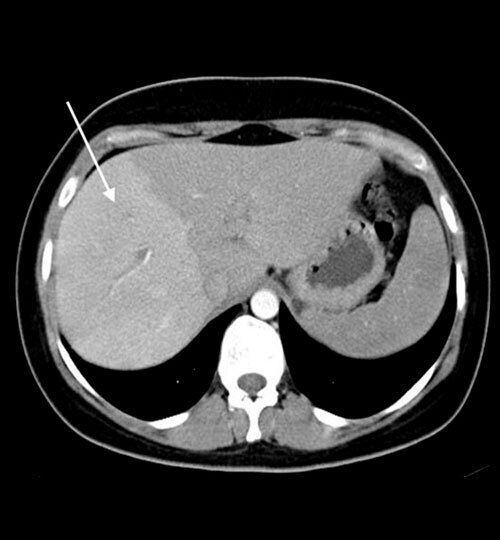

Dumortier J, Ronot M, Beaufrère A. Quand penser à une maladie vasculaire du foie  ?  Rev Prat 2025 ;75(10) :1081 - 5.